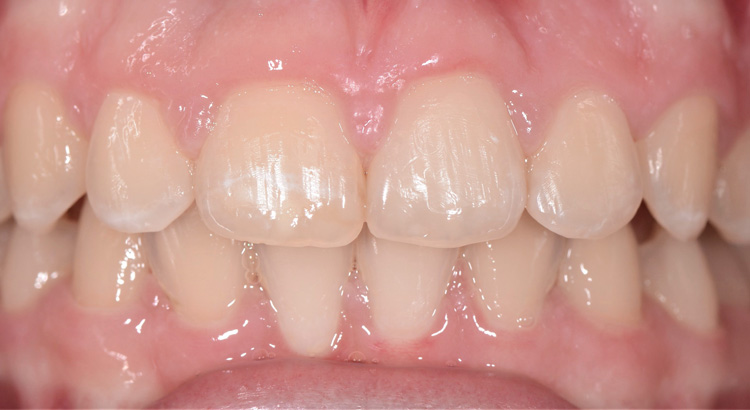

Odontoiatria Estetica

Questo giovane paziente vuole migliorare l’estetica del suo sorriso preservando però il suo dente da eventuali interventi sullo smalto. In particolare vuole cambiare la forma dell’incisivo centrale e diminuire gli spazietti neri tra gli incisivi laterali e i canini. Grazie all’utilizzo di materiali compositi ad alta esteticità è stato possibile ripristinare la corretta estetica del sorriso. Paziente contentissimo del suo nuovo sorriso.